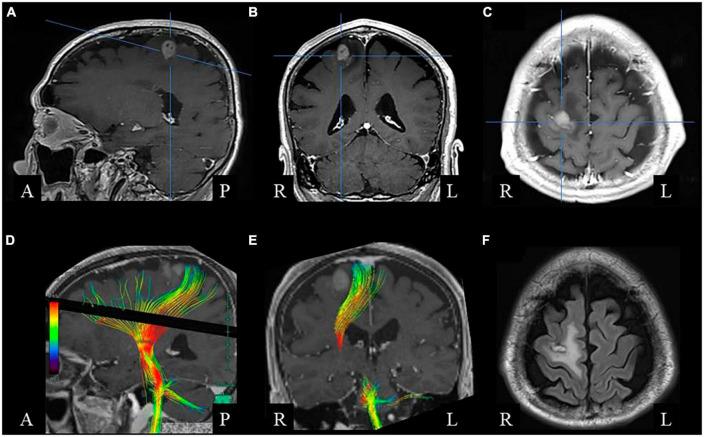

The mechanisms underlying bimanual coordination have not yet been fully elucidated. Here, we evaluated the clinical features of bimanual movement impairment in a patient following surgery for a frontal lobe tumor. The patient was an 80-year-old man who had undergone subtotal tumor resection for a tumor in the right superior frontal gyrus. Histological examination of the resected specimen led to the diagnosis of malignant lymphoma of the diffuse large B-cell type, and the patient subsequently received high-dose methotrexate-based chemotherapy. Postoperatively, the patient had difficulty with bimanual movement, and on the 5th postoperative day we found that the impairment could not be attributed to weakness. Temporal changes in the characteristics of manual movements were analyzed. Bimanual diadochokinesis (opening/closing of the hands, pronation/supination of the forearms, and sequential finger movements) was more disturbed than unilateral movements; in-phase movements were more severely impaired than anti-phase movements. Bimanual movement performance was better when cued using an auditory metronome. On the 15th postoperative day, movements improved. The present observations show that in addition to the disturbance of anti-phase bimanual movements, resection of the frontal lobe involving the supplementary motor area (SMA) and premotor cortex (PMC) can cause transient impairment of in-phase bimanual diadochokinesis, which can be more severe than the impairment of anti-phase movements. The effect of auditory cueing on bimanual skills may be useful in the diagnosis of anatomical localization of the superior frontal gyrus and functional localization of the SMA and PMC and in rehabilitation of patients with brain tumors, as in the case of degenerative movement disorders.

双手协调的潜在机制尚未完全阐明。在此,我们评估了一名额叶肿瘤手术后患者双手运动障碍的临床特征。该患者为一名80岁男性,因右侧额上回肿瘤接受了肿瘤次全切除术。对切除标本的组织学检查确诊为弥漫性大B细胞型恶性淋巴瘤,患者随后接受了以大剂量甲氨蝶呤为基础的化疗。术后,患者双手运动困难,在术后第5天我们发现这种障碍并非由无力所致。分析了手部运动特征的时间变化。双手轮替动作(双手的张开/闭合、前臂的旋前/旋后以及手指的顺序运动)比单侧运动受干扰更严重;同相运动比反相运动受损更严重。使用听觉节拍器提示时,双手运动表现更好。术后第15天,运动有所改善。目前的观察结果表明,除了反相双手运动受到干扰外,涉及辅助运动区(SMA)和运动前皮质(PMC)的额叶切除可导致同相双手轮替动作暂时受损,且这种受损可能比反相运动的受损更严重。听觉提示对双手技能的影响可能有助于诊断额上回的解剖定位以及SMA和PMC的功能定位,也有助于脑肿瘤患者的康复,就像在退行性运动障碍的情况下一样。